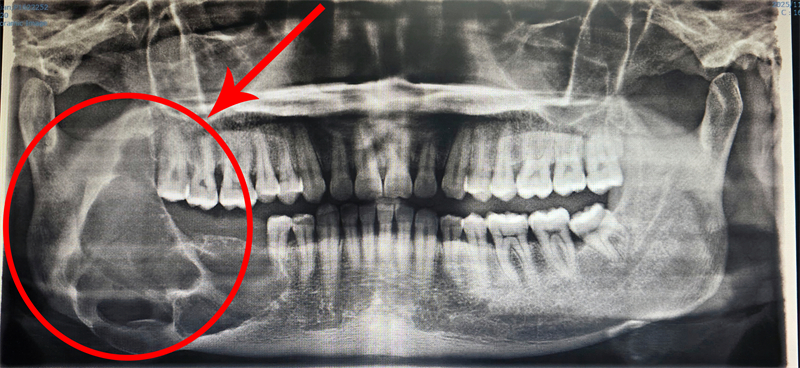

口腔颌面外科陈裕聪副主任医师接诊后,第一时间感受到患者的焦虑与无助,当即安排全面影像学检查。检查结果显示,成釉细胞瘤已然复发,病变范围大幅扩大,右下颌骨升支遭严重破坏,若拖延治疗,不仅会导致面部畸形,更会造成不可逆的功能障碍。

深知患者的迫切需求,手术团队反复研读影像报告,结合患者身体状况反复推演,最终量身定制“数字化手术导板+腓骨移植”的个性化治疗方案。